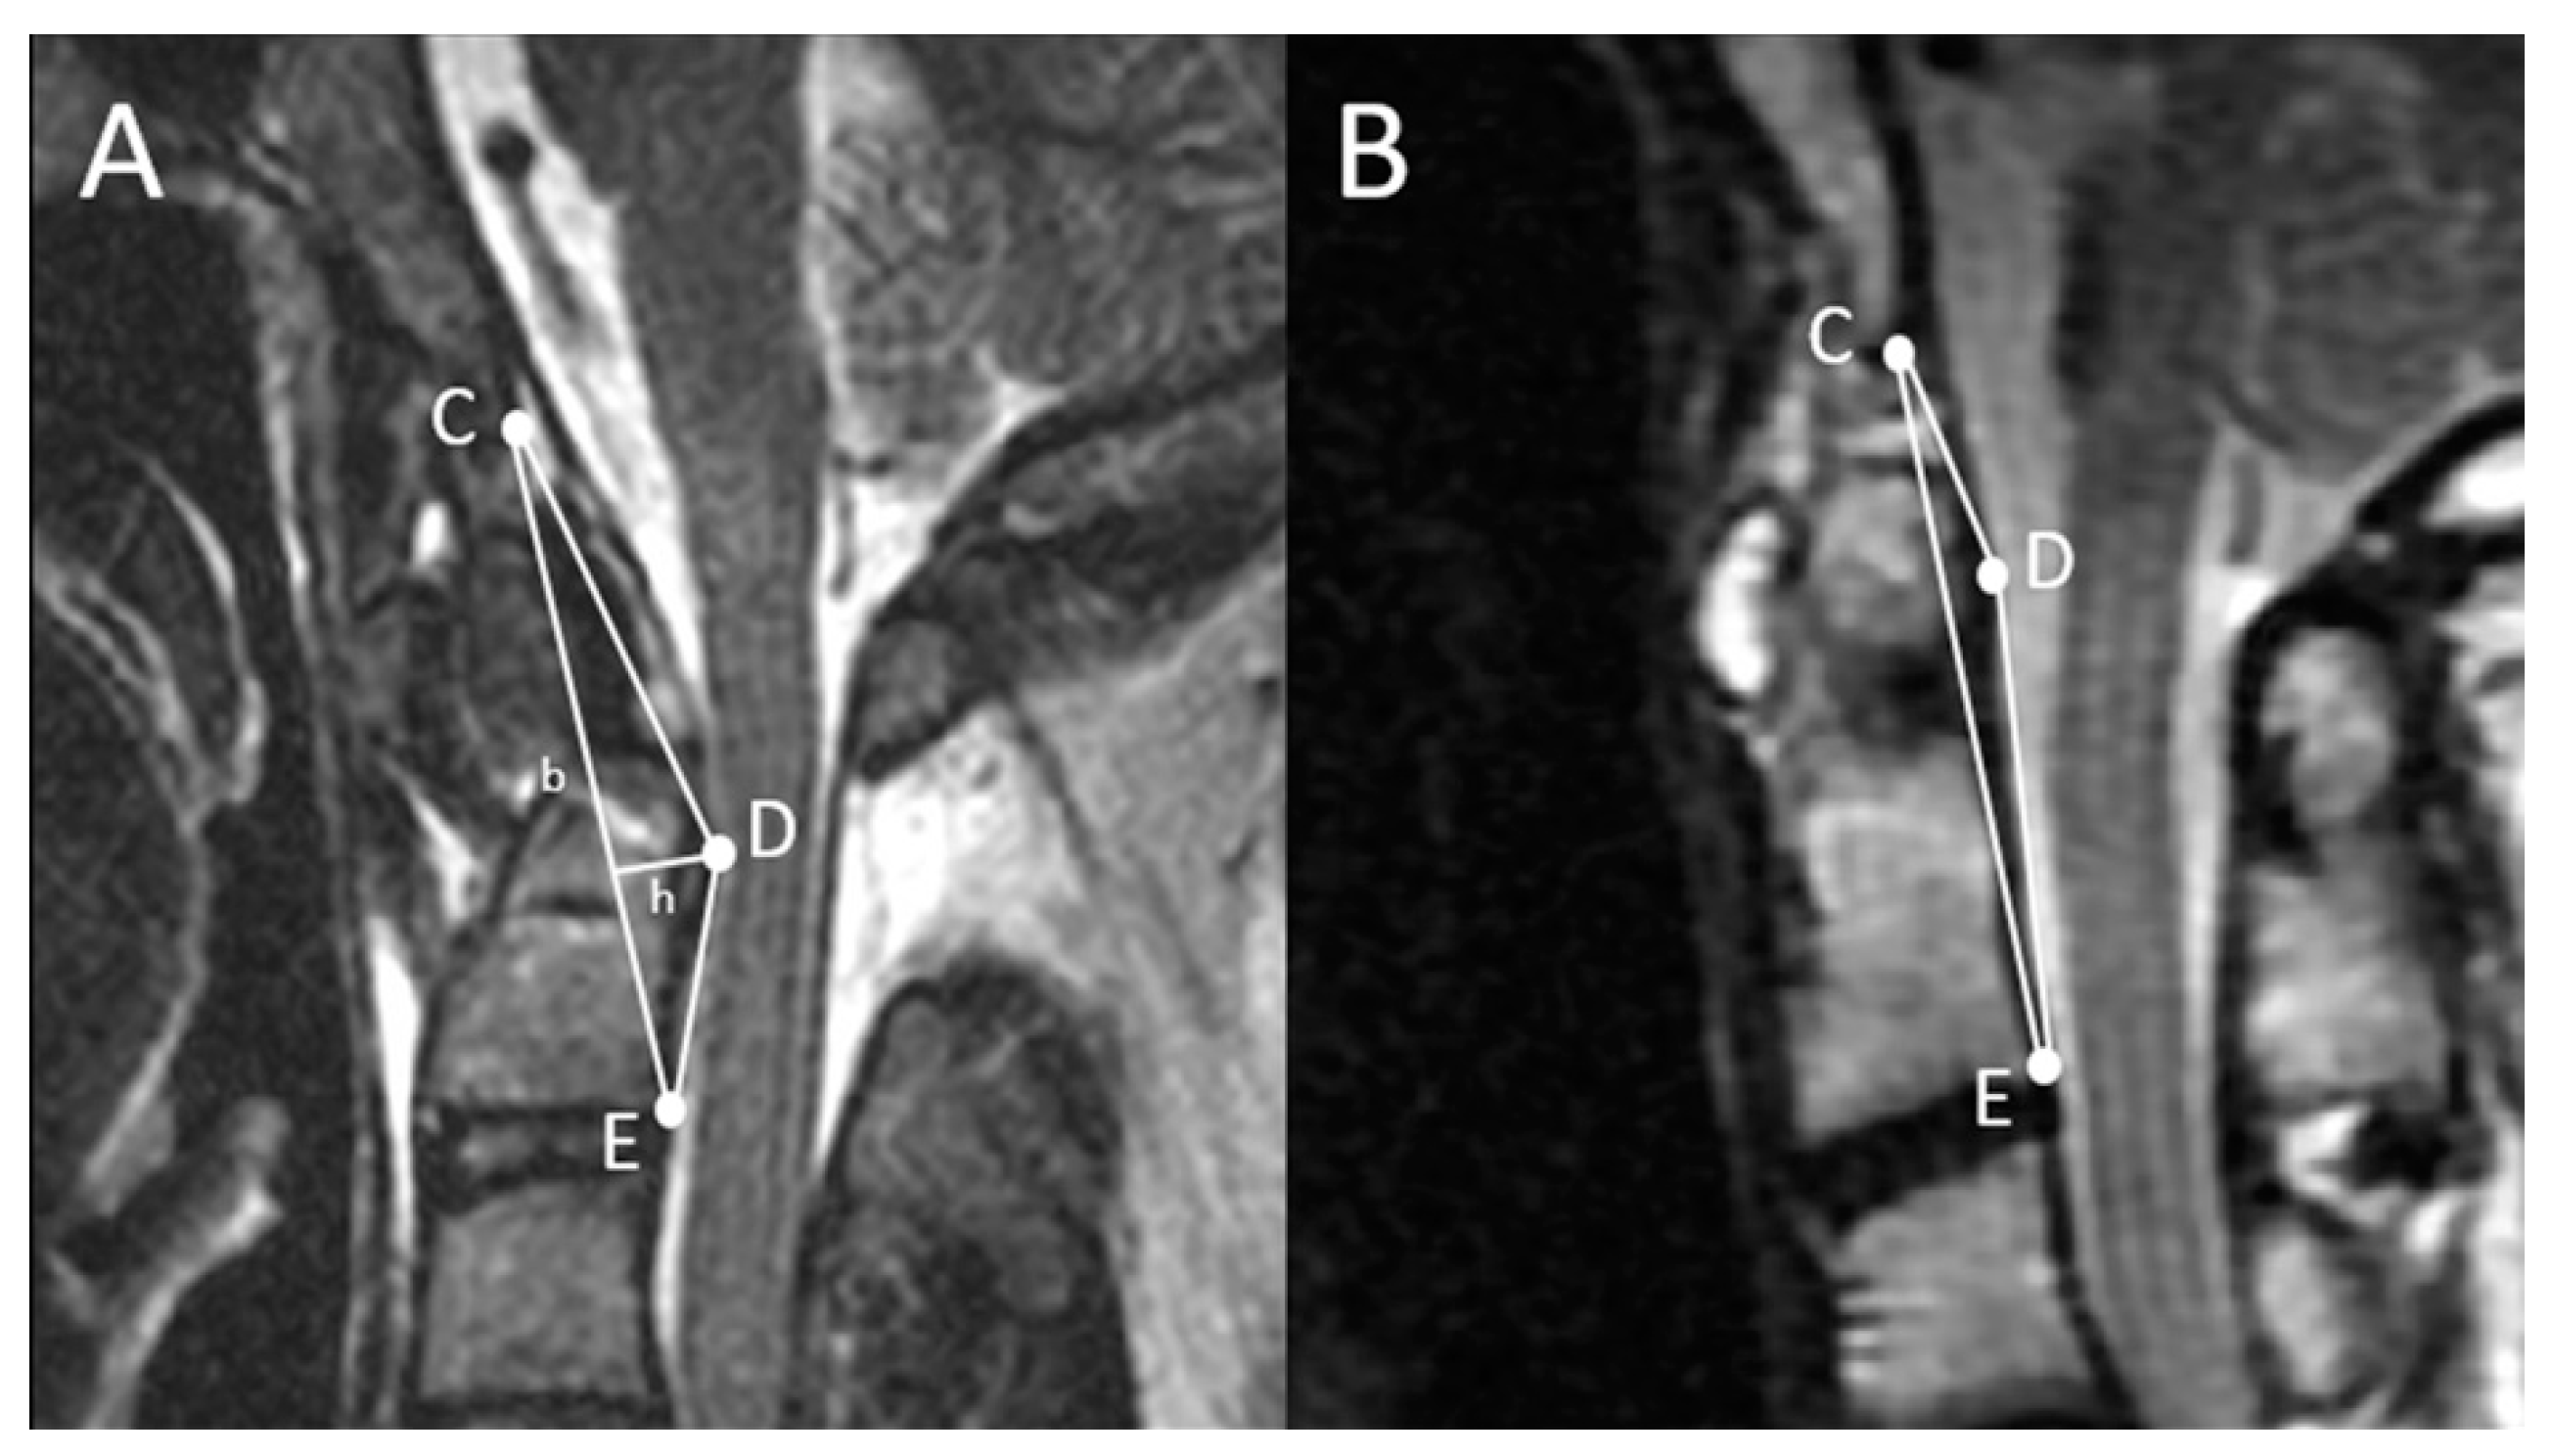

Figure 1.

Proposed assessment of ventral compression at the craniovertebral junction (CVJ) by using a simulated triangle. The three points of the triangle are the lowest point of the clivus (C), the posterior-inferior point of the axial vertebral body (E), and the most indenting point of the pathology (D). The triangular area can be calculated as follows: (b × h)/2. Demonstration of the pre-operation (A) and post-operation (B) triangular area (TA) after atlantoaxial fixation.

MRI is the diagnostic modality of choice for disorders at the CVJ because MRI overcomes the limitation of X-rays in soft tissue differentiation. For example, in patients with RA who present with retro-dental pannus formation, the spinal cord compression can hardly be appreciated by radiographs, but are easily depicted by MRI. Moreover, the conventional X-ray based radiological measurements of CVJ anomalies are infrequently correlated with the prognosis of management, since soft tissues and nerves are hardly taken into account. To mitigate the above-mentioned shortcomings, the current study aimed to validate an MRI-based measurement used for the quantification of neural tissue compression at the CVJ and evaluation of the efficacy of its surgical management. The triangular area (TA) of the CVJ, proposed by Chang et al. [6], is a novel measurement that can quantify the degree of compression caused by basilar invagination. The value of the TA of the CVJ is defined by the area determined by three points in the mid-sagittal T2 weighted image: The lowest point of the clivus, the posterior-inferior point of the C2 vertebral body, and the most dorsal indentation point in the ventral aspect of the brain stem (Figure 1). The area can be calculated by most of the viewer applications currently available. The paper by Chang et al. in 2016 analyzed a cohort of BI patients who required odontoidectomy; the TA reportedly represented well the degree of ventral compression and was successfully decreased after decompression and subsequent atlantoaxial fixation.

2.2. Radiographical Definition of the Triangular Area of the Cranio-Vertebral Junction (the TA of the CVJ)

In the mid-sagittal T2-weighted MRIs of each patient, a triangular area ventral to the brainstem was delineated on the picture archiving and communication system (PACS) and calculated by its viewer. The TA was defined by three points: The lowest point of the clivus, the posterior-inferior point of the C-2 vertebral body, and the most dorsal indentation point in the ventral aspect of the brain stem [6]. For the surgical cases, adequate decompression and successful reduction was determined by post-operative CT scans and dynamic lateral radiographs. Patients whose post-operative ADI < 3 mm in AAS cases or a realigned posterior cortex of the C2 vertebra in odontoid fracture cases were considered as having complete reduction.